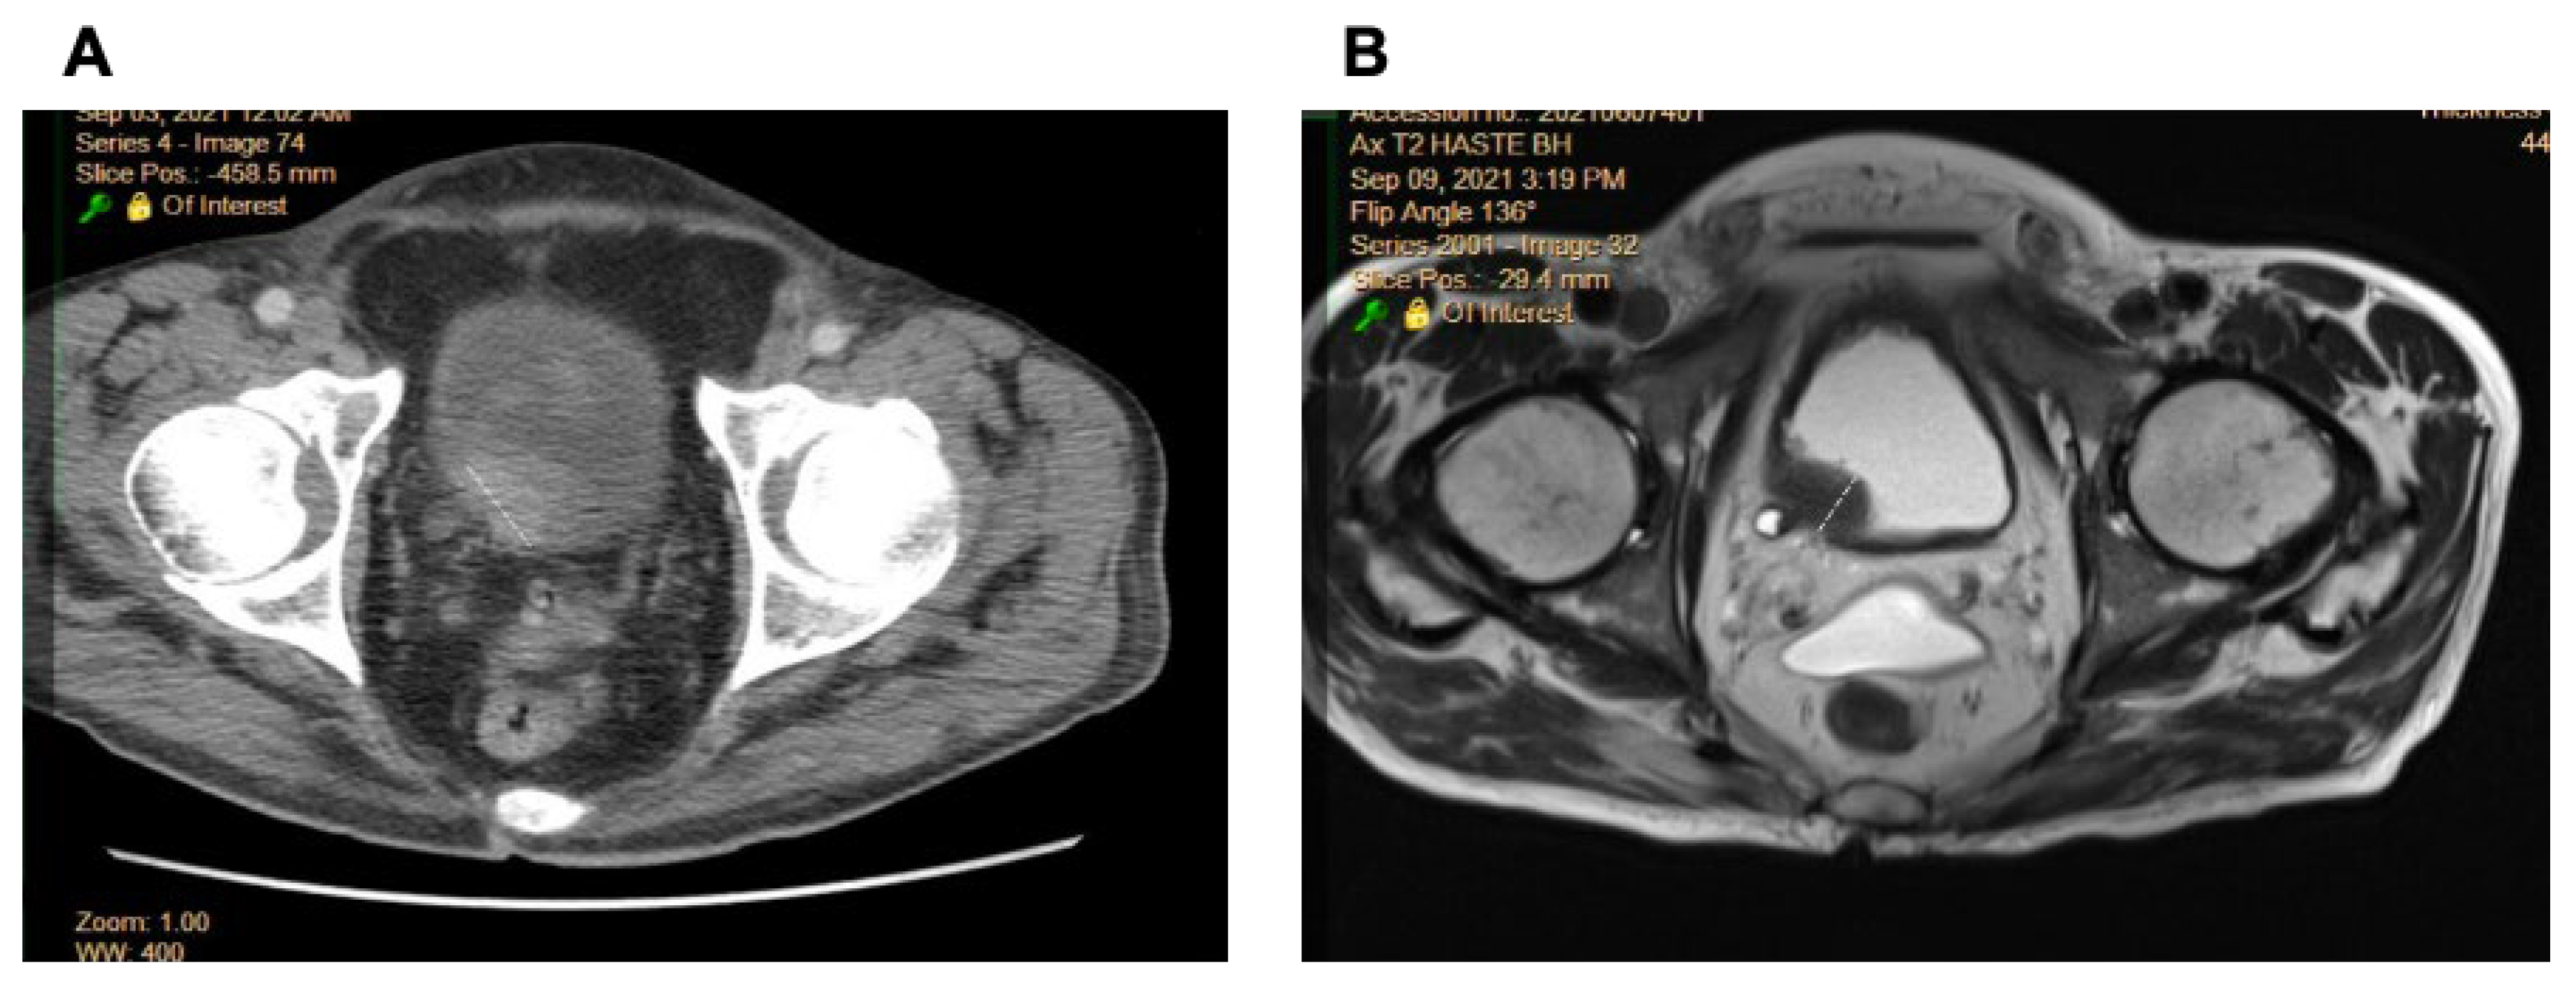

2.1. Comparison of Radiologic Interpretation on CT and MR Images

4.3. Radiologic Staging of BCa

4.4. Radiomics Analysis of CT and MR Images